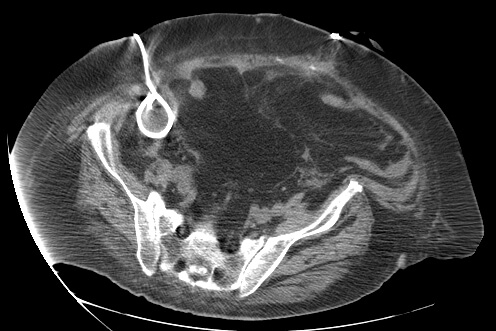

23 year old female with fever and RLQ tenderness s/p appendectomy.

Comment: This case demonstrates performance of a straight-forward CT-guided drainage. Once the abscess was localized on CT and the access site confirmed with a 25g needle, the collection was accessed with a Chiba needle and a guidewire was coiled within the collection. Serial dilatation was then performed so that a pigtail drainage catheter could be placed within the collection for drainage.